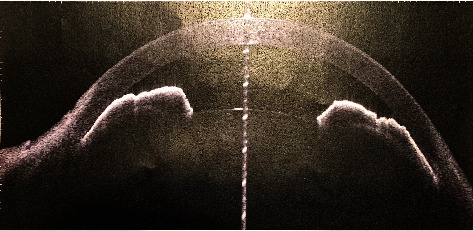

Abstract Image